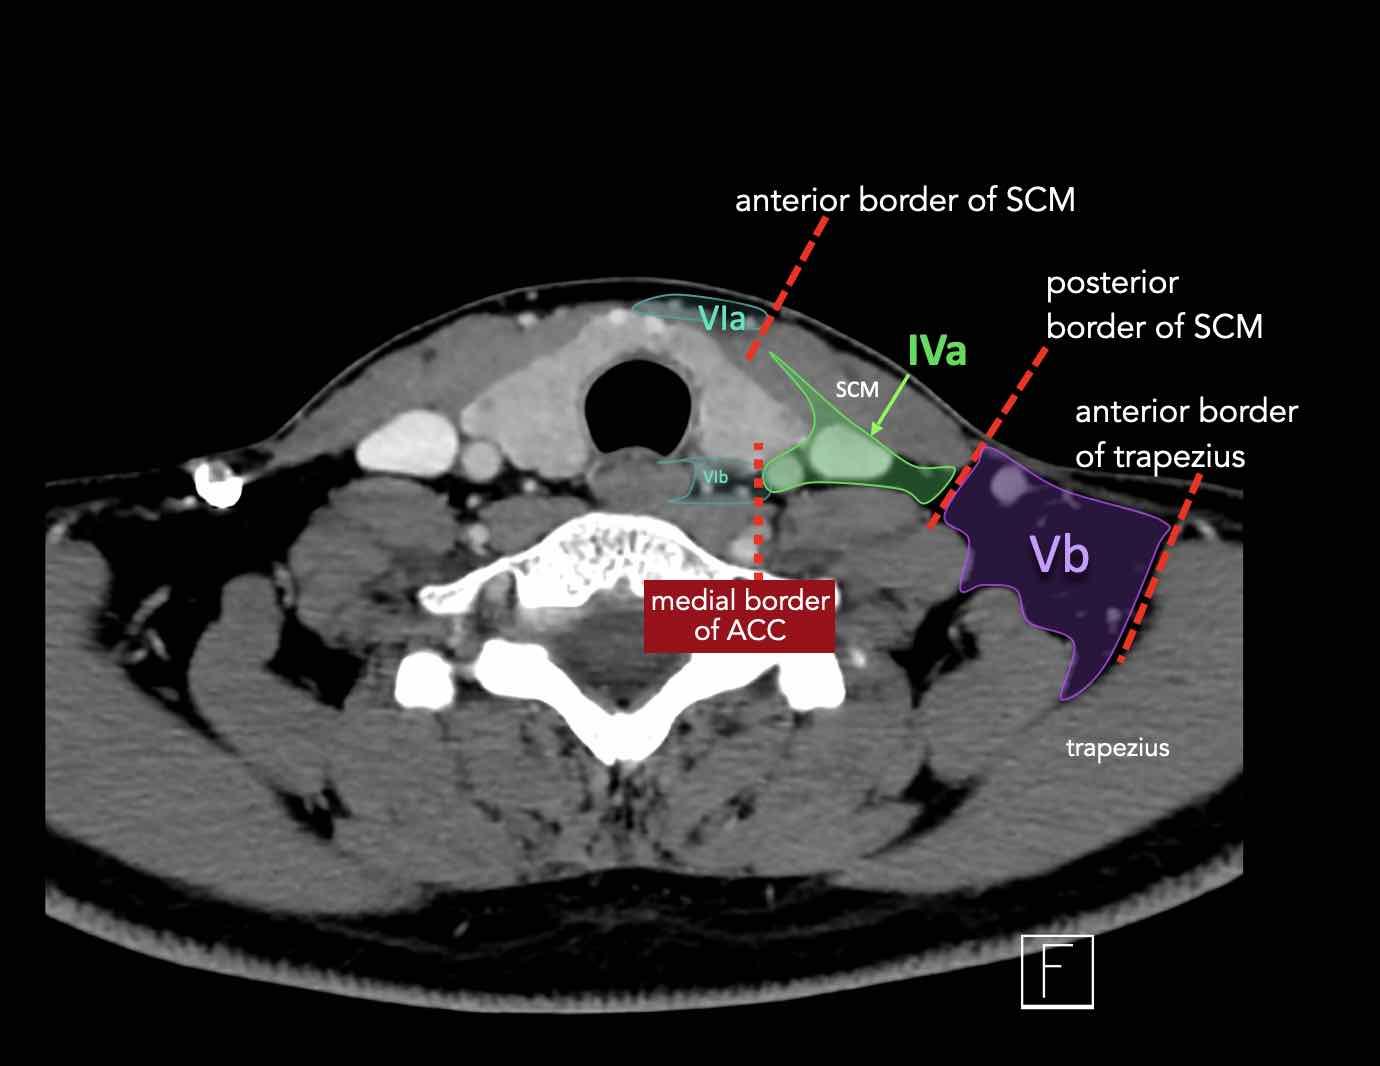

CT Scan Mặt Cắt Ngang (Axial CT)

Các lát cắt CT mặt phẳng ngang tương ứng với hình minh họa tổng quan.

Các lát cắt CT mặt phẳng ngang với hình ảnh chi tiết hơn.

Nhấp vào hình ảnh để phóng to.

IV – Tĩnh mạch cảnh dưới và hố thượng đòn trong

Ranh giới giữa tầng IVa và IVb được xác định tùy ý tại vị trí 2 cm phía trên khớp ức đòn.

Tầng IVa

Các hạch này có nguy cơ chứa di căn từ các ung thư hạ hầu, thanh quản, tuyến giáp và thực quản cổ.

Hiếm gặp hơn, di căn từ khoang miệng trước có thể biểu hiện tại vị trí này với tổn thương hạch gần tối thiểu hoặc không có.

Tầng IVb

Các hạch này có nguy cơ chứa di căn từ các ung thư hạ hầu, thanh quản dưới thanh môn, khí quản, tuyến giáp và thực quản cổ.

V – Tam giác cổ sau và hố thượng đòn

Tầng V chứa các hạch của nhóm tam giác cổ sau nằm ở phía sau cơ ức đòn chũm, xung quanh phần dưới của thần kinh phụ gai sống và các mạch máu cổ ngang.

VI – Cổ trước